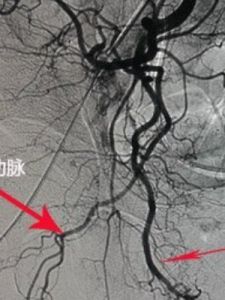

傳統上,異常勃起分為原發、特發或繼發。在血流動力學上,可被分為2種不同的類型:低流型(缺血)及高流型(非缺血)。由於低流狀態是由於靜脈的阻塞而高流狀態是由於動脈血流的增加,Witt等(1990)進行了新的分類:靜脈阻塞性及動脈性。異常勃起可表現為急性、間歇性或慢性。生理上,陰莖軟縮狀態海綿體血氣水平與系統靜脈血相似,勃起時達到動脈水平。必須記住,每1例異常勃起均開始於正常生理勃起,海綿體血氧水平正常。高流型海綿體血氧水平正常,但低流型6h後,血氣顯示缺血及酸中毒徵象。當有疑問時,血氣分析及雙功超聲檢查有助於鑑別診斷。研究發現,低流型異常勃起海綿體造影靜脈回流延遲至15min,動脈造影僅有背動脈及球動脈顯影。高流型異常勃起海綿體造影及動脈造影顯示靜脈回流加快、破裂的海綿體動脈使海綿體血液淤積。

海綿體造影亦可鑑別兩型靜脈阻塞時血流停滯;動脈型則海綿體血液回流迅速彩色超聲Doppler檢查低血流量型顯示動脈血流極少海綿體膨脹;高血流量型在血管損傷區可顯示動脈破裂和異常血池。

⑵高血流量型莖異常勃起:早期局部冰袋冷敷使血管收縮破壞的血管可能自發形成血栓多數海綿體動脈破裂不能自行癒合常需要陰部內動脈造影和栓塞有報導動脈內注射亞甲藍脈腔注入自體血凝塊栓塞治療近年有成功的報導。